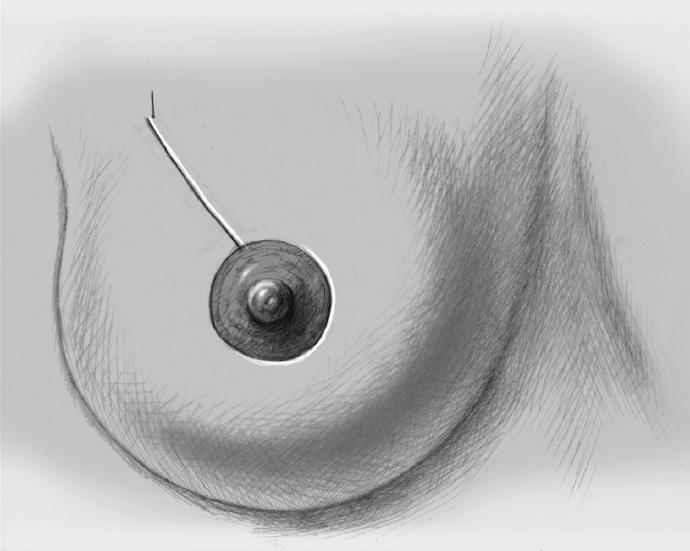

The skin is closed in two layers with recentering of the nipple–areola complex using interrupted sutures (Vicryl 3–0) according to the preoperative de-epithelialization pattern, which can be corrected at this time.

The skin is closed with an intracutaneous continuous monofilament suture.

After establishing the final position of the nipple–areola complex, the marked area of skin is excised precisely over the nipple. To facilitate positioning, a retaining suture can be placed in the nipple at the 12-o’clock position; this allows assessment of any tension on the nipple (e.g., due to the internal fixation). Following skin excision, the nipple can be readily guided to its new position using the retaining suture.

The nipple is repositioned at the most cranial point of the measured periareolar de-epithelialization area. If nipple repositioning over a long distance is necessary, a domelike extension in a cranial direction can be de-epithelialized beyond the purely periareolar de-epithelialization area (LeJour technique).

The bigger, outer ring of skin is approximated to the smaller inner ring: a gathering subdermal purse string suture is placed along the outer ring, largely adjusting this to the smaller inner ring. This is followed by the normal two-layer approximation. The excess skin shrinks well when it is sufficiently elastic.

The technique can be modified with a periareolar incision with segmental (medial or lateral) or vertical (inferior) extension. If the diameter of the periareolar ring becomes greater than 10 cm, this extension is advisable, as the extreme creasing of the skin produced when the ring is bigger persists even after healing. Segmental or vertical extension and skin resection makes the ring smaller and leads to further tautening of the skin.